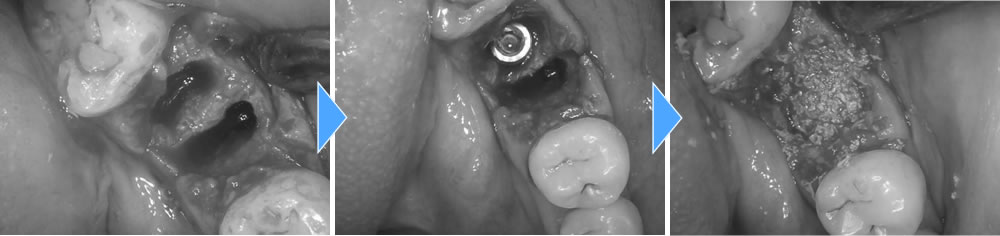

まずは当該歯を抜歯し、中に溜まっている膿を全て掻き出しました。次にインプラントの埋入、骨の無くなってしまう部分に骨を作る処置(骨造成)までを1度のオペで行いました。手術から4週間後に抜糸を行いました。

4ヵ月後に2次オペを行い、完全閉鎖をしている歯茎よりインプラント体の頭を出して骨とインプラント体がオステオインテグレーション(結合)している事を確認しました。